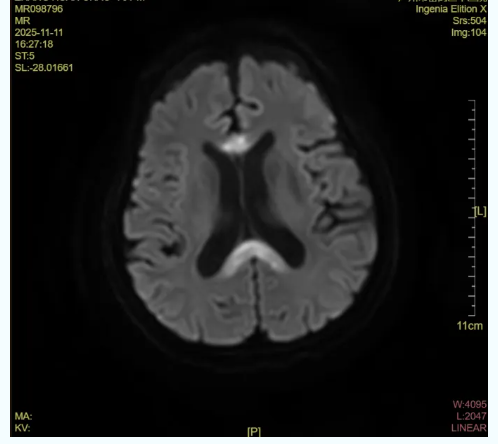

外院曾诊断为“多发性腔梗”,但患者转入时处于昏睡状态,全身无力、无法言语,且痰液多无法咳出。接诊医生发现,其病灶位置与临床表现并不完全吻合,必须找出真正的病因。最终,经神经内科、影像科等多学科团队协作,通过颅脑磁共振(MR)检查,确诊为原发性胼胝体变性(MBD)——因长期酗酒所引发的致命脑病。

“胼胝体是左右脑交换信息的‘桥梁’,而长期酗酒及营养不良(特别是维生素B1严重缺乏)会直接损伤这条‘电缆’,导致语言、运动、记忆信号完全‘断联’。”重症医学科主任高江宝提醒,MBD的预警信号包括突发口齿不清、双手震颤,类似中风但更为凶险;出现抽搐、意识模糊,这是酒精严重毒害神经系统的警报;以及嗜睡、无法进食等大脑功能衰竭的晚期表现。